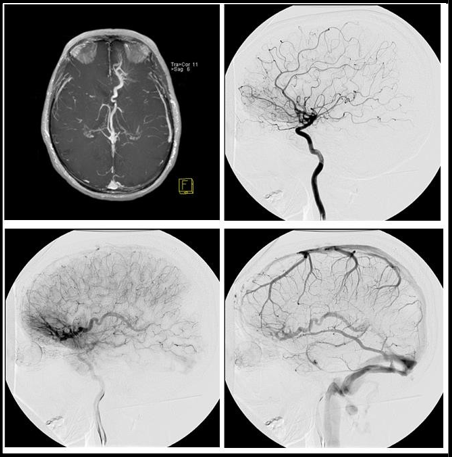

Three patients presented on this series were seen in the clinic for different reasons: One 50 years- old man was investigating recent onset of seizures, another woman aged 45 had an incidental finding during the investigation of a headache and the last one was a young woman (age 28) studied with DSA during the procedure of stereotactic radiosurgery after an episode of intracerebral hemorrhage attributed to a vascular abnormality seen on a DSA’s arterial phase. The first 2 patients were not treated for the vascular abnormality. The images seen on MR and DSA are presented in Figures 1 to 3.

Figure 1: (A) MR showing an enlarged vein with the classic pattern developmental venous anomaly (caput medusa). Lateral view sequence (B, C and D) of digital subtraction angiography demonstrating the presence of a large early draining vein, with the classical aspect of venous angioma.